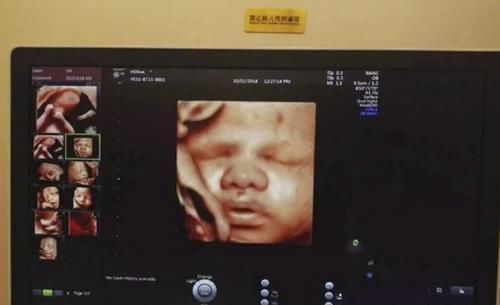

近日里,一段新生婴儿的视频走红,被网友们誉为最美新生儿,更是直接把比美的赛道拉到了产房里。

可这最美新生儿仿佛一出生就开了挂,视频里的他眼睛明亮,五官端正,皮肤看起来洁白光滑。

更让人称奇的是这宝宝仿佛天生自带镜头感,看着他亲爱的妈妈并且微笑着和镜头互动,那一笑真的是如天使降临般温暖,暖化了万千网友的心,也难怪大家纷纷称这个小宝宝为最美新生儿了。

就连经历过无数次新生儿降生的助产士都惊叹道,在产房这么多年,生下来就这么可爱有灵性的小宝宝真的特别少见。